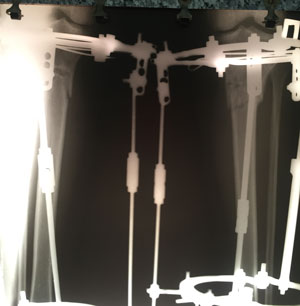

Дата операции - 15.07.2019г.

Дата снятия аппаратов - 15.10.2019г.

Срок сращения 90 дней.